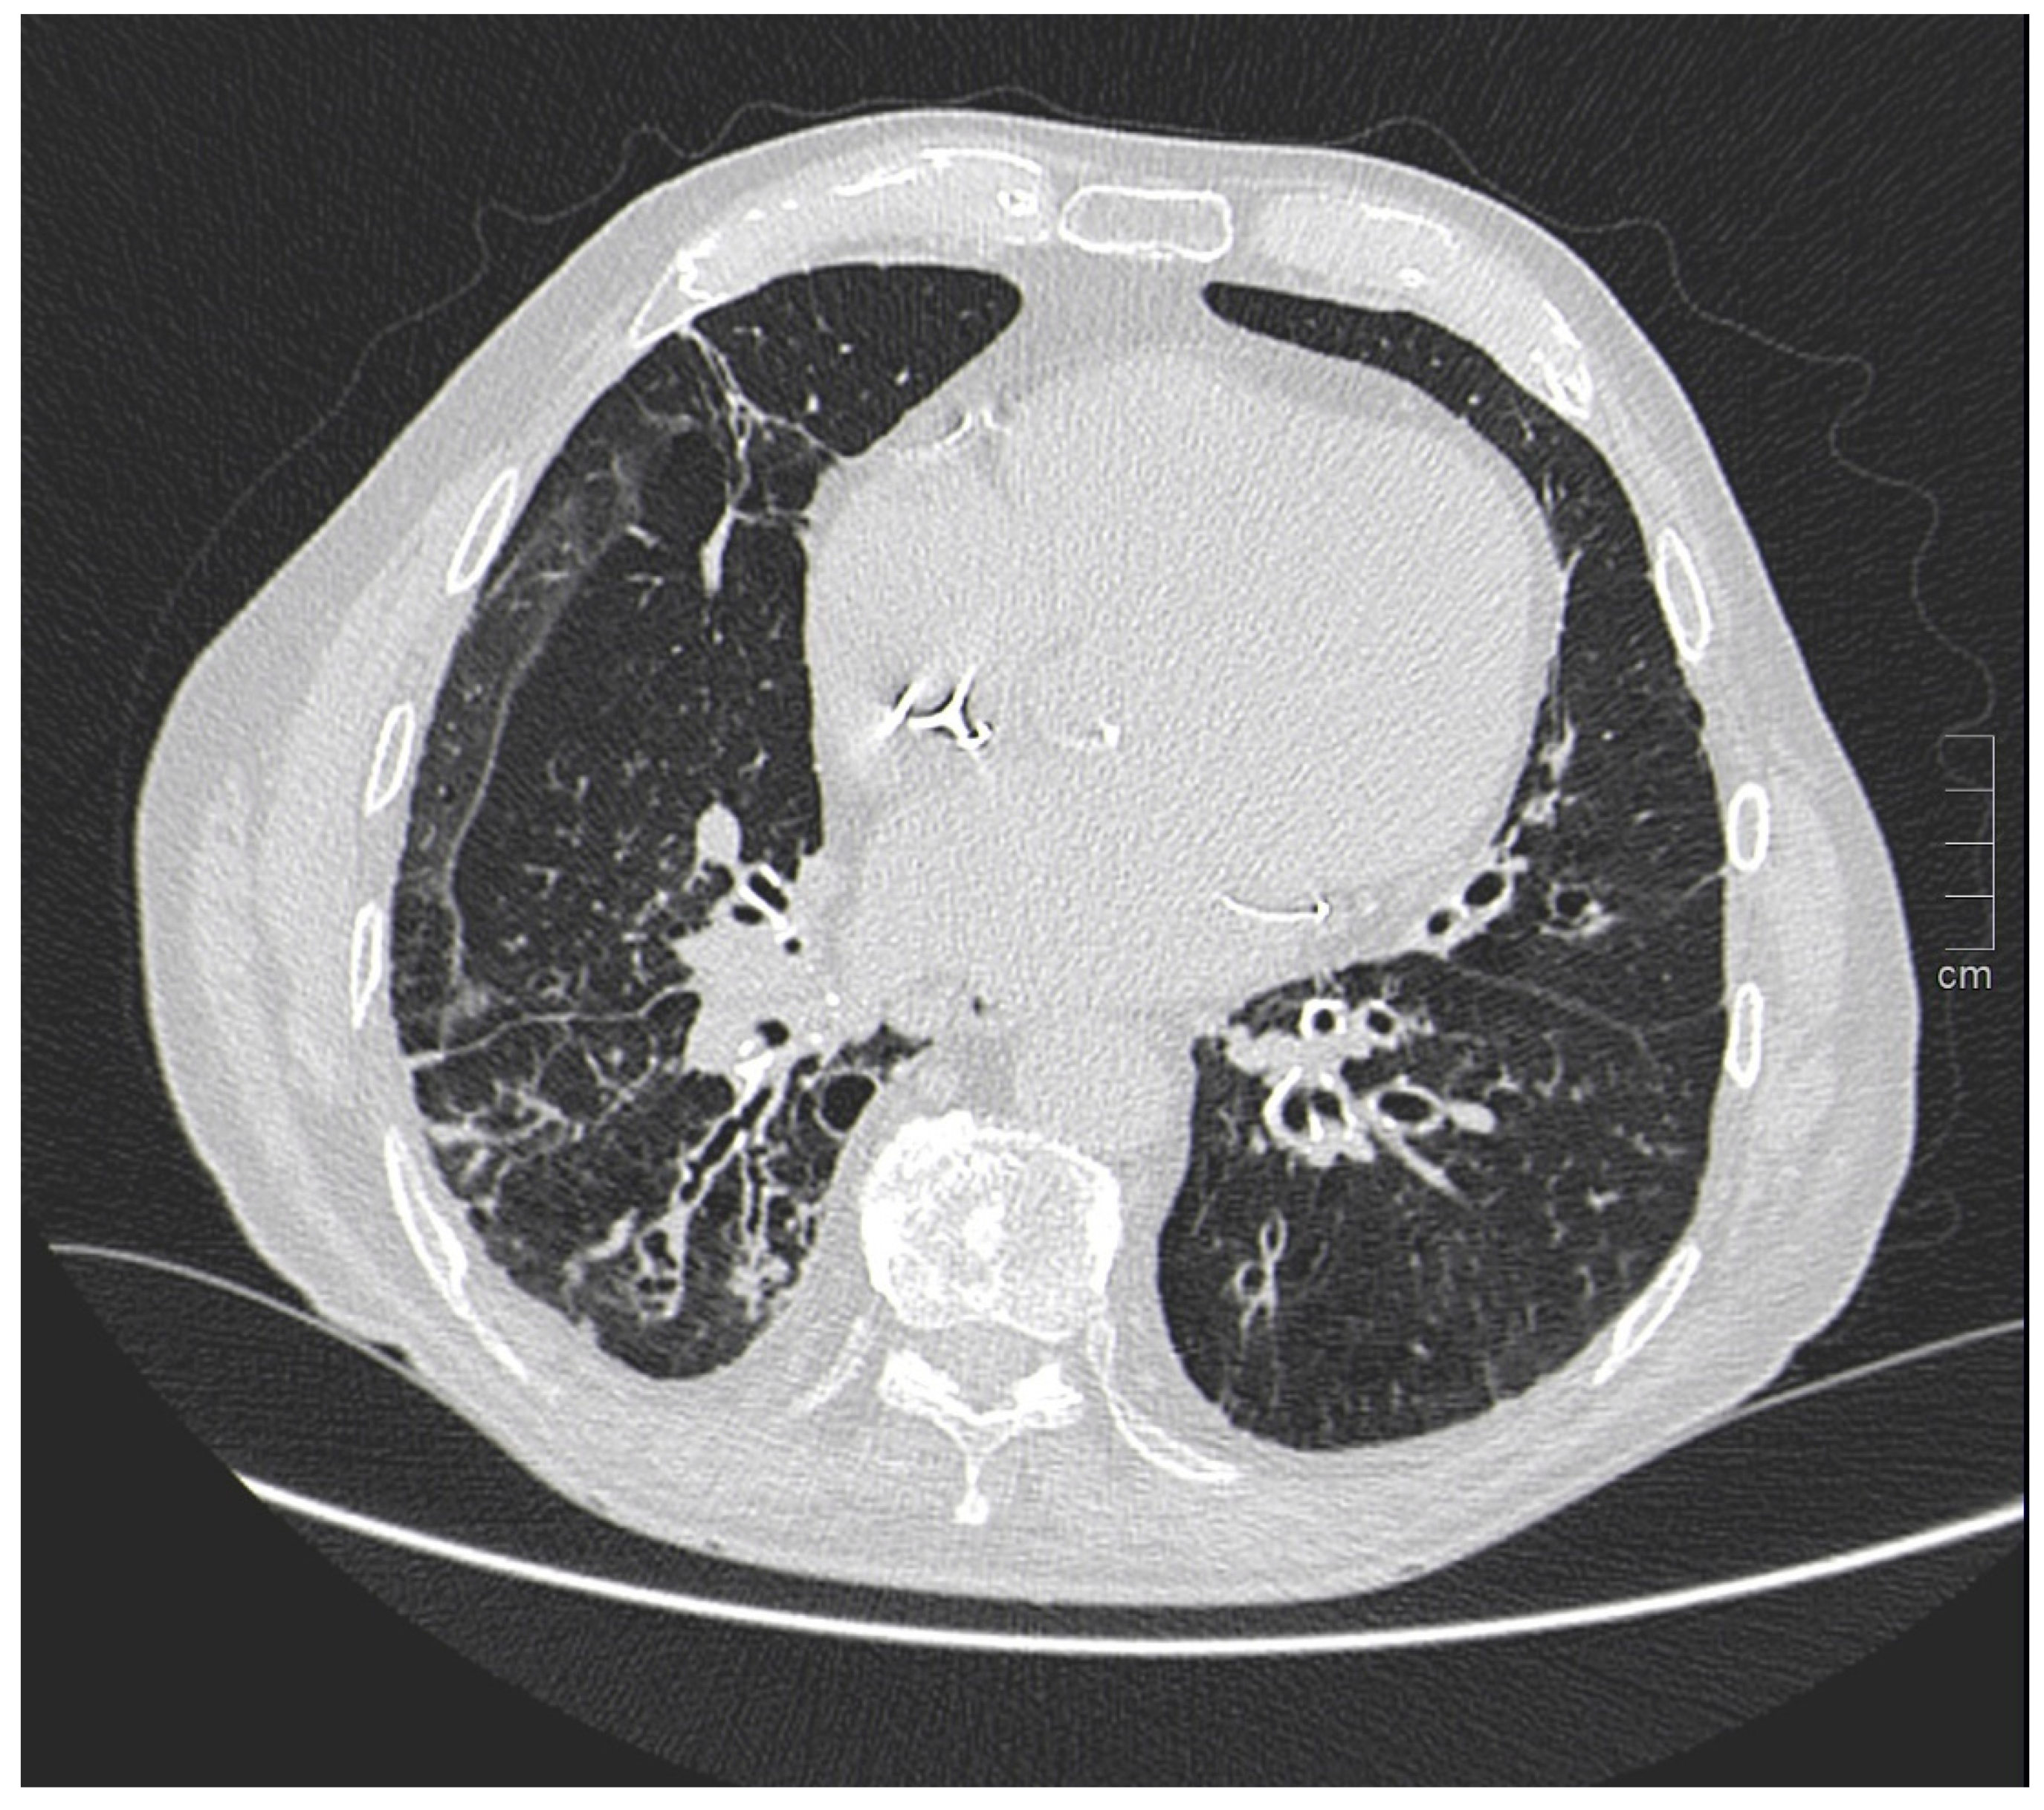

Kim et al. [29] in a study evaluated gender differences regarding the distribution and prevalence of CAC, its relationship to clinical risk factors, and the effect of a high calcium score (≥100) on subsequent initiation of medical therapy by evaluating a court of 542 individuals, of whom 279 were female and 263 were male. The data demonstrated an increasing CAC score with age, regardless of sex. However, women showed significantly lower CAC scores than men in the same age group. The lower CAC scores in women are likely in part indicative of the fact that women have a greater amount of non-calcifying plaque, so-called low-attenuation plaque, than men, indicating that lower CAC scores may actually be related to higher-risk plaque. However, there are also cases, although less frequent, of men with low-attenuation atheromasic plaque (Figure 1). Another interesting finding emerged from the correlation between CAC and clinical risk factors: for both sexes, age had a similar effect on CAC score (OR 1.11 and 1.12, respectively); however, in men, obesity showed a significant effect on CAC score (OR 2.16), while in women, smoking showed a significant effect on CAC score (OR 4.27). This result clearly demonstrated that the traditional clinical risk factors and which women, therefore, share with men actually have different clinical impact in the two genders. Finally, it was investigated how the CAC score result affected the further management of men vs. women with a CAC score ≥100 when adjusted for concurrent coronary CTA findings (moderate to severe lesions vs. non-obstructive lesions) in initiating aspirin and statin therapy [29].

Figure 1.

Male, 39-years-old, patients with history of dyslipidemia, type-1 obesity, and higher level of stress at work. The patient reported a non-anginal chest pain for which an ergometric ECG stress test was performed, and the results were negative. According to the Diamond–Forrester score, the patient was first categorized as a low pre-test probability risk of having CAD. To correctly rule-out CAD, the patients underwent CCTA examination, which showed a severe non-calcific plaque in the distal right coronary artery (white arrowhead).